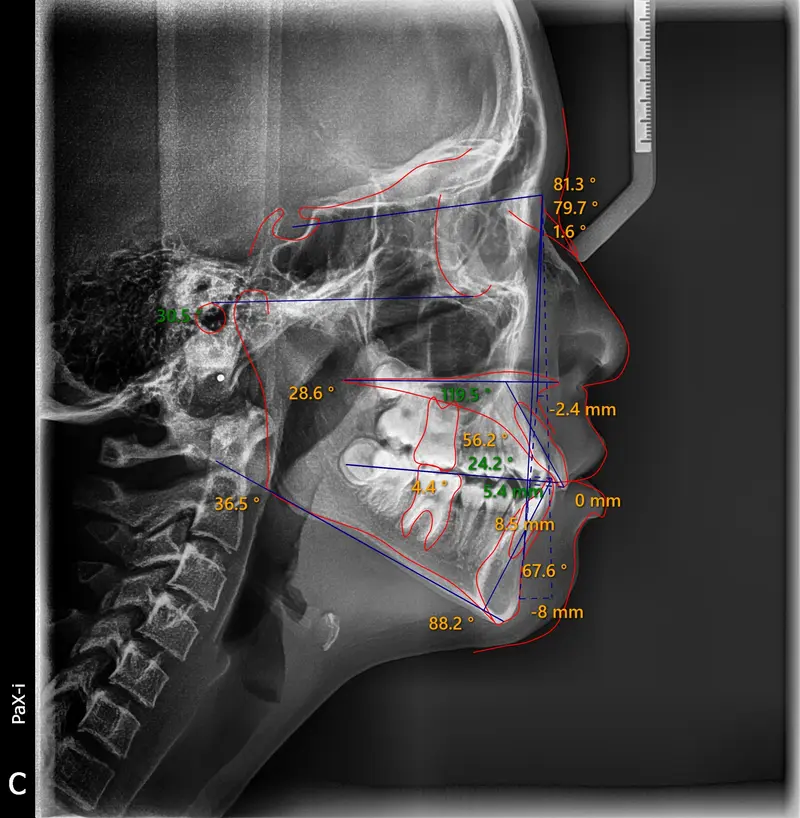

The Diagnosis

Bimaxillary protrusion (teeth flaring forward) causing lip incompetence. The patient struggled to close his lips comfortably, straining the chin muscle (mentalis).

The Engineering

A strategic extraction plan (4 premolars) allowed us to retract the front teeth. Note the dramatic improvement in chin projection and facial balance. The extractions did not flatten the face; they harmonized it.